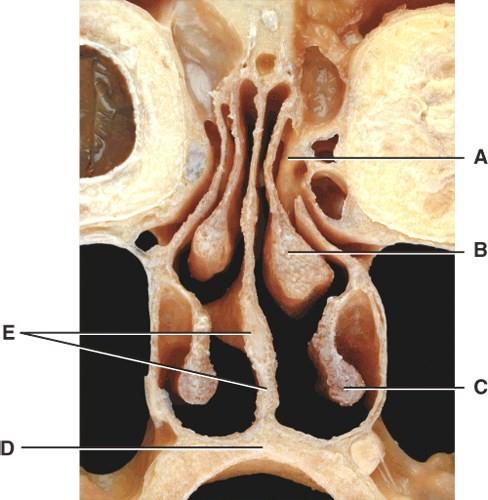

Where are the olfactory receptors found?

- A

- B

- C

- D

- U

B

Where is the middle nasal concha?

- A

- B

- C

- D

- E

B

Where is the inferior nasal concha?

- A

- B

- C

- D

- E

C

What is E pointing to?

- Soft palate

- Ethmoid bone

- Hard palate

- Nasal septum

- Air cells

D